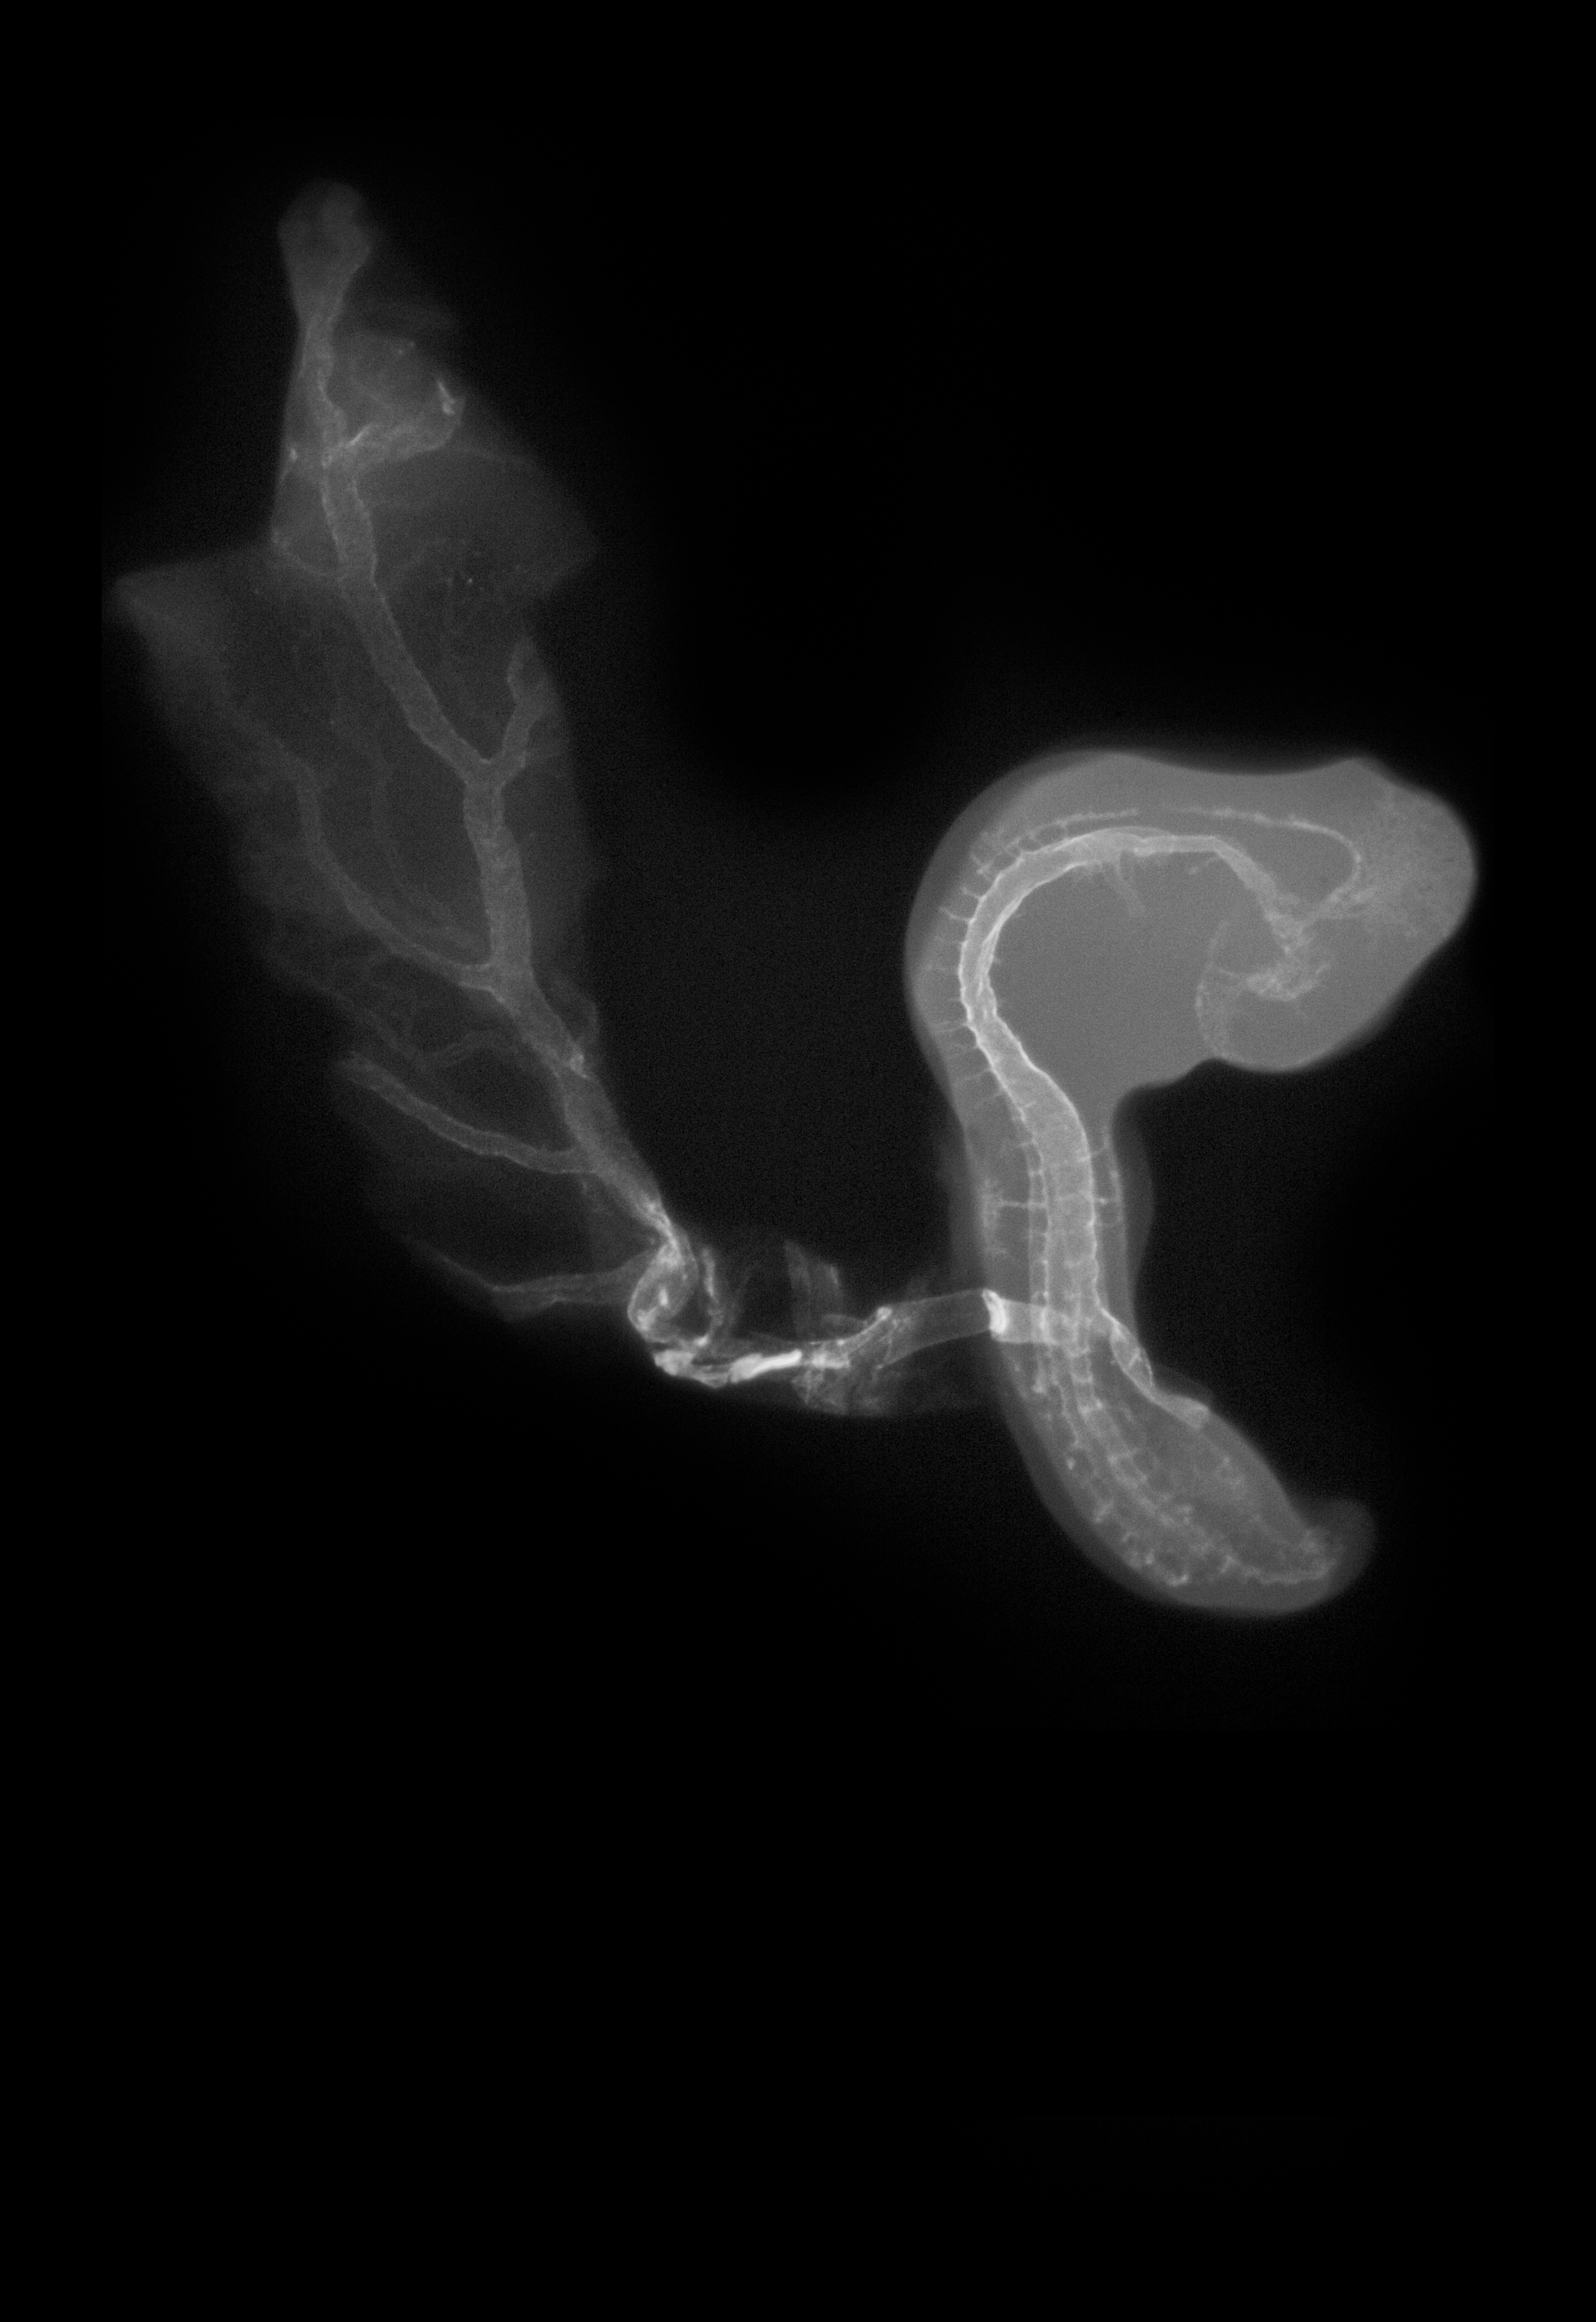

Chick Embryo Microangiography

Hamburger-Hamilton (HH) Stage 18 (approx. 3 days)

Stereo X-Ray Micrographs